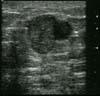

Abcès

Tableau inflammatoire caractéristique.

- Zone périphérique dense hypoéchogène englobant la peau et le bord supérieur du lobe,

- Zone centrale hypoéchogène hétérogène pouvant rapidement augmenter de volume avec aspect polylacunaire étendu.